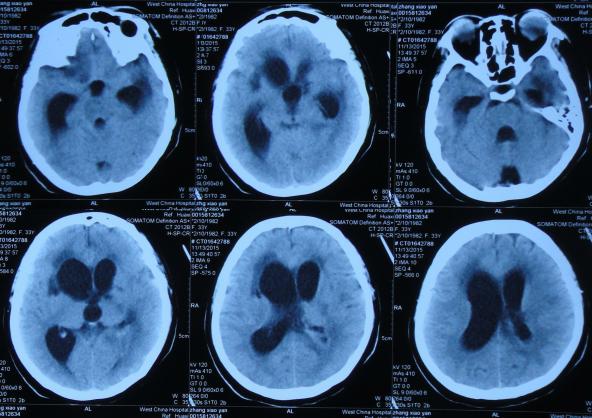

第1家医院治疗13天后即2015年8月16日,查头CT:双侧侧脑室,三脑室及四脑室扩张(图-4),且给予腰穿检查,提示颅压高(脑脊液检查结果不详),给予相关对症治疗。

图-4:2015年8月16日头部CT

第1家医院治疗16天后即2015年8月19日,间断头痛,腰穿颅内压仍高,查头部CT示脑室进一步扩张(图-5)。

图-5:2015年8月19日头部CT